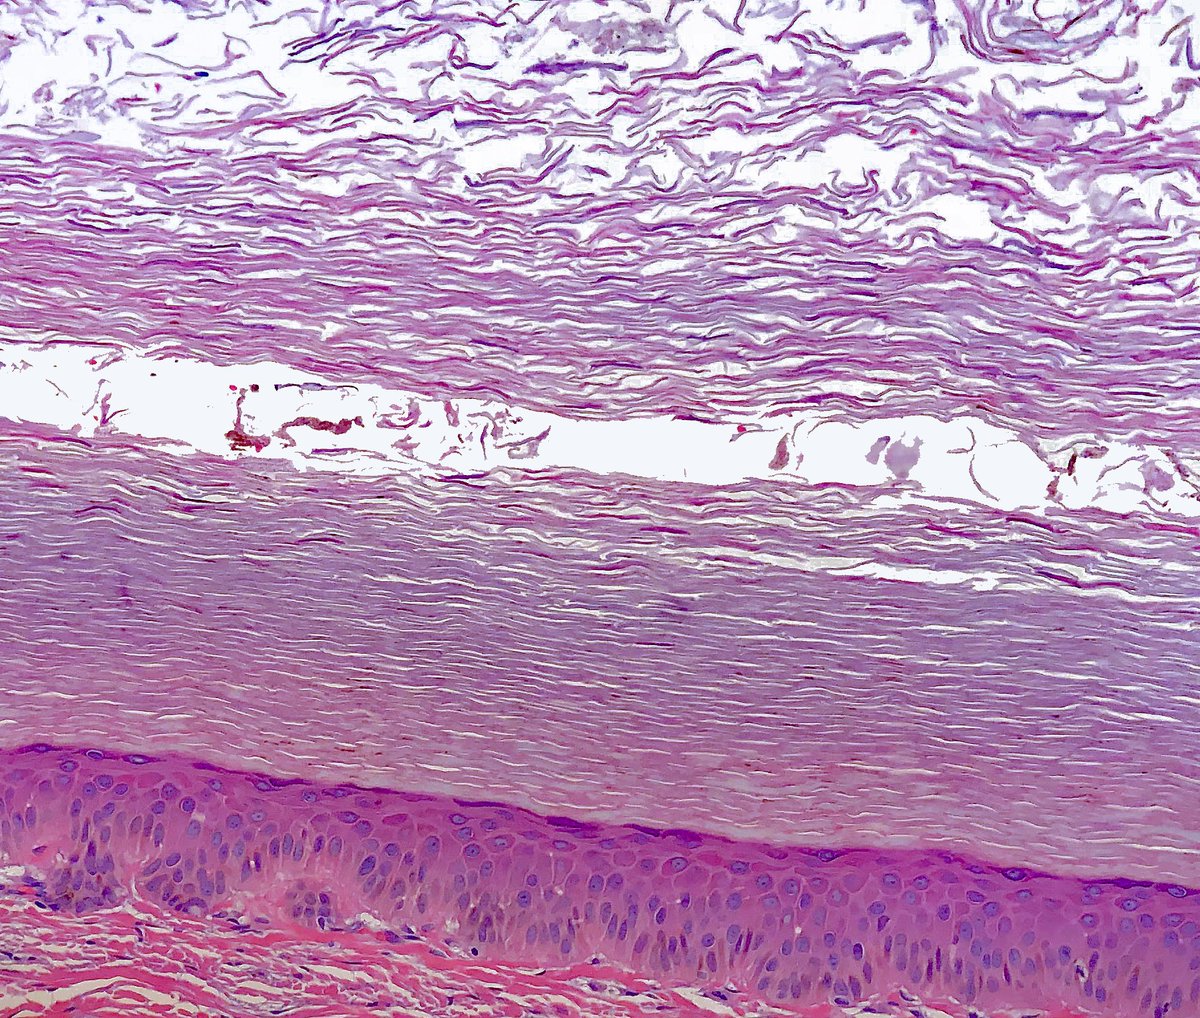

Adult, lower leg, scaly lesion - reactive perforating collagenosis. Really pleasing to look at.

#dermpath#pathology#dermatology pic.twitter.com/JFl4dKEpeT